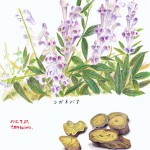

黄芩

シソ科のコガネバナの周皮を除いた根。

性味:苦・寒

帰経:肺・脾 ・大腸・小腸・胆

主な効能と応用:

①清熱燥湿:湿温・暑温初期の湿熱欝阻気機による、

胸苦しい・腹が張る・悪心・嘔吐・尿が濃いなどの症候に用いる。

方剤例⇒黄芩滑石湯

②清熱瀉火・解毒・凉血:肺熱の咳嗽・呼吸促迫・黄痰などの症候時に用いる。

方剤例⇒清肺湯

③清熱安胎:妊娠中の蘊熱による下腹痛などに用いる。

方剤例⇒当帰散

備考:他薬の配合により様々な効用を示す。

柴胡と往来寒熱を除き、白芍と下痢を抑え、桑白皮と肺火を除き、

白朮と安胎に働き、山梔子と胸膈火熱を除き、荊芥・防風と肌表の熱を清解する。